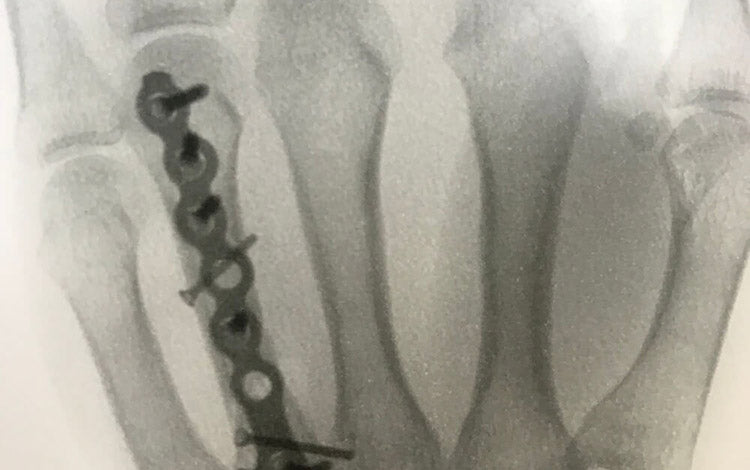

I work with a lot of clients who are recovering from injury- mountain bike related and other. And recently I managed a decent one myself. I'd like to say it was a spectacular jump, but mostly it was a speed where I should've slowed, immediately followed by a pile of limbs, my bike, what I suspect was a concussion, a dislocation and according to my surgeon an exploded hand.

So how do can you maximise your recovery when you get that new bit of bling fitted to hold you back together? Or even the smaller, yet equally frustrating injuries like muscle sprains and strains?